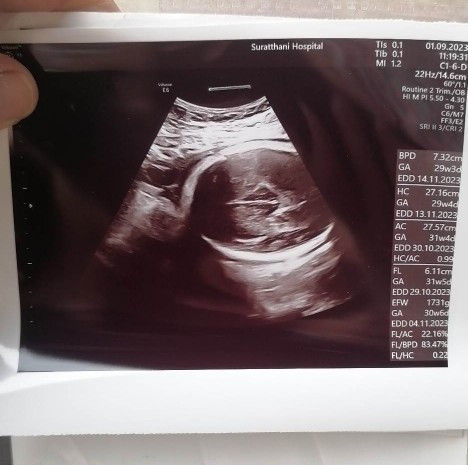

อายุครรภ์32วีก4วันแล้วคะ หมอบอกว่า50/50ไม่รู้ว่าผู้หญิงรึผช.อยากสอบถามแม่ๆคะว่าได้ผญ.รึผช.พอจะดูออกไหมคะ